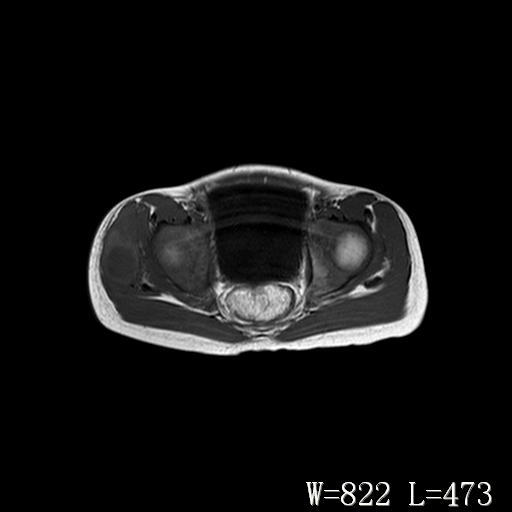

男,6岁,发现右臀部肿块10余天。

右侧臀部较大囊性肿块,长t1、长t2信号改变,周围组织信号正常,不知有否局部注射史?如果有,则支持脓肿,否则要考虑血管瘤可能。